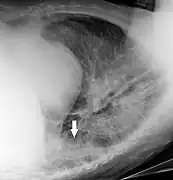

Chest

_chest_radiograph_(X-ray).jpg.webp)

Chest radiographs are used to diagnose many conditions involving the chest wall, including its bones, and also structures contained within the thoracic cavity including the lungs, heart, and great vessels. Conditions commonly identified by chest radiography include pneumonia, pneumothorax, interstitial lung disease, heart failure, bone fracture and hiatal hernia. Typically an erect postero-anterior (PA) projection is the preferred projection. Chest radiographs are also used to screen for job-related lung disease in industries such as mining where workers are exposed to dust.[12]

For some conditions of the chest, radiography is good for screening but poor for diagnosis. When a condition is suspected based on chest radiography, additional imaging of the chest can be obtained to definitively diagnose the condition or to provide evidence in favor of the diagnosis suggested by initial chest radiography. Unless a fractured rib is suspected of being displaced, and therefore likely to cause damage to the lungs and other tissue structures, an X-ray of the chest is not necessary as it will not alter patient management.